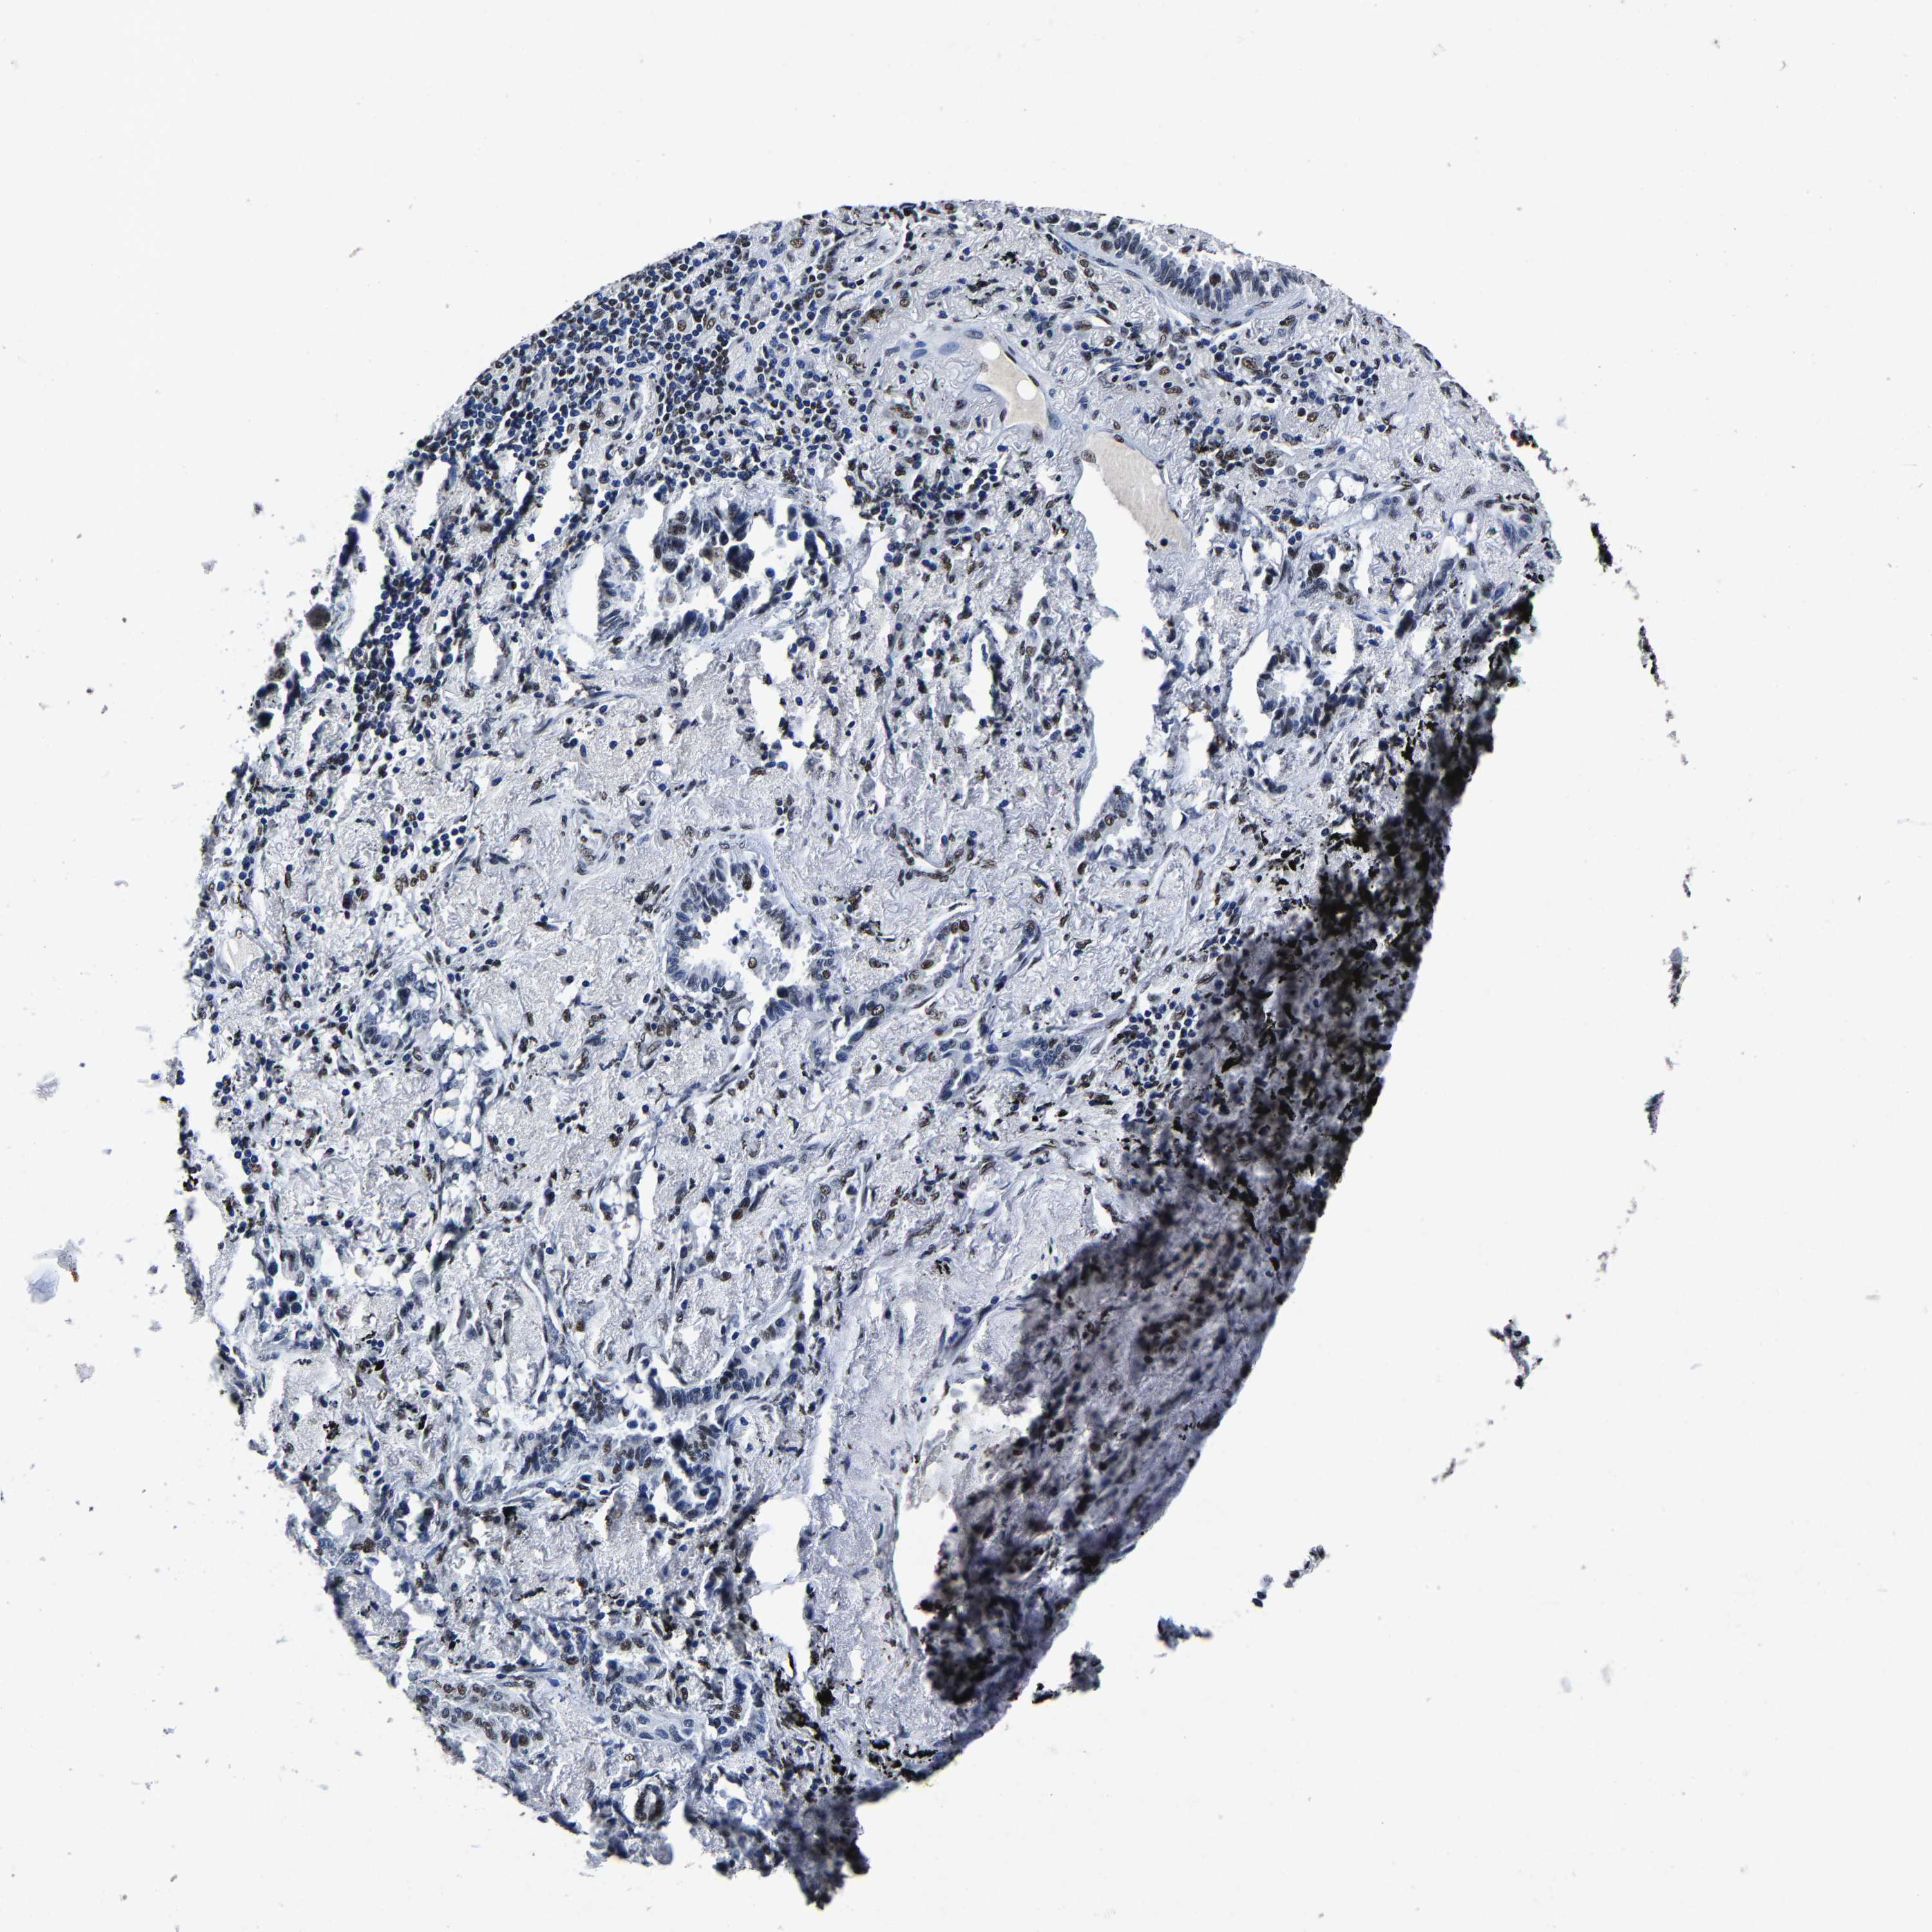

LUNG SQUAMOUS CELL CARCINOMA (TCGA) - Interactive survival scatter ploti

The Survival Scatter plot shows the clinical status (i.e. dead or alive) for all individuals in the patient cohort, based on the same data that underlies the corresponding Kaplan-Meier plots. Patients that are alive at last time for follow-up are shown in blue and patients who have died during the study are shown in red.

The x-axis shows the expression levels (FPKM) of the investigated gene in the tumor tissue at the time of diagnosis. The y-axis shows the follow-up time after diagnosis (years). Both axes are complimented with kernel density curves demonstrating the data density over the axes. The top density plot shows the expression levels (FPKM) distribution among dead (red) and alive patients (blue). The right density plot shows the data density of the survived years of dead patients with high and low expression levels respectively, stratified using the cutoff indicated by the vertical dashed line through the Survival Scatter plot. This cutoff is automatically defined based on the FPKM cutoff that minimizes the p-score. The cutoff can be changed by dragging the vertical line or by entering a cutoff value in the square labeled "Current cut-off".

Under the Survival Scatter plot the p-score landscape (black curve; left axis) is shown together with dead median separation (red curve; right axis). Dead median separation is the difference in median mRNA expression between patients who have died with high and low expression, respectively. It is calculated as follows: median FPKM expression of dead patients with high expression - median FPKM expression of dead patients with low expression. This is intended to aid the user in visually exploring custom cutoffs and the associated p-scores and dead median separation.

Individual patient data is displayed and can be filtered by clicking on one or more of the category buttons on the top of the page. Categories describing expression level and patient information include: high, low, alive, dead, female, male and tumor stages. The scale of the x-axis can be toggled between linear and log-scale by clicking on the "x log" button. Mouse-over function shows TCGA ID, patient information and mRNA expression (FPKM) for each patient.

& Survival analysisi

Kaplan-Meier plots summarize results from analysis of correlation between mRNA expression level and patient survival. Patients were divided based on level of expression into one of the two groups "low" (under cut off) or "high" (over cut off). X-axis shows time for survival (years) and y-axis shows the probability of survival, where 1.0 corresponds to 100 percent.

RBM45 is not prognostic in Lung Squamous Cell Carcinoma (TCGA)

Best expression cut offi

Based on the FPKM value of each gene, patients were classified into two groups and association between prognosis (survival) and gene expression (FPKM) was examined. The best expression cut-off refers the FPKM value that yields maximal difference with regard to survival between the two groups at the lowest log-rank P-value. Best expression cut-off was selected based on survival analysis .

When clicking on this number, the vertical dashed line indicating cut-off, the interactive survival plot, and the Kaplan-Meier curve will be adjusted to show results based on the best expression cut-off.

: 7.94

P scorei

Log-rank P value for Kaplan-Meier plot showing results from analysis of correlation between mRNA expression level and patient survival.

N/A

TCGA RNA samplesi

RNA-seq data is reported as average FPKM (number Fragments Per Kilobase of exon per Million reads), generated by the The Cancer Genome Atlas (TCGA) .

Normal distribution across the dataset is visualized with box plots, shown as median and 25th and 75th percentiles. Points are displayed as outliers if they are above or below 1.5 times the interquartile range. FPKM values of the individual samples are presented next to the box plot.

Average pTPM 8.9

Number of samples 489